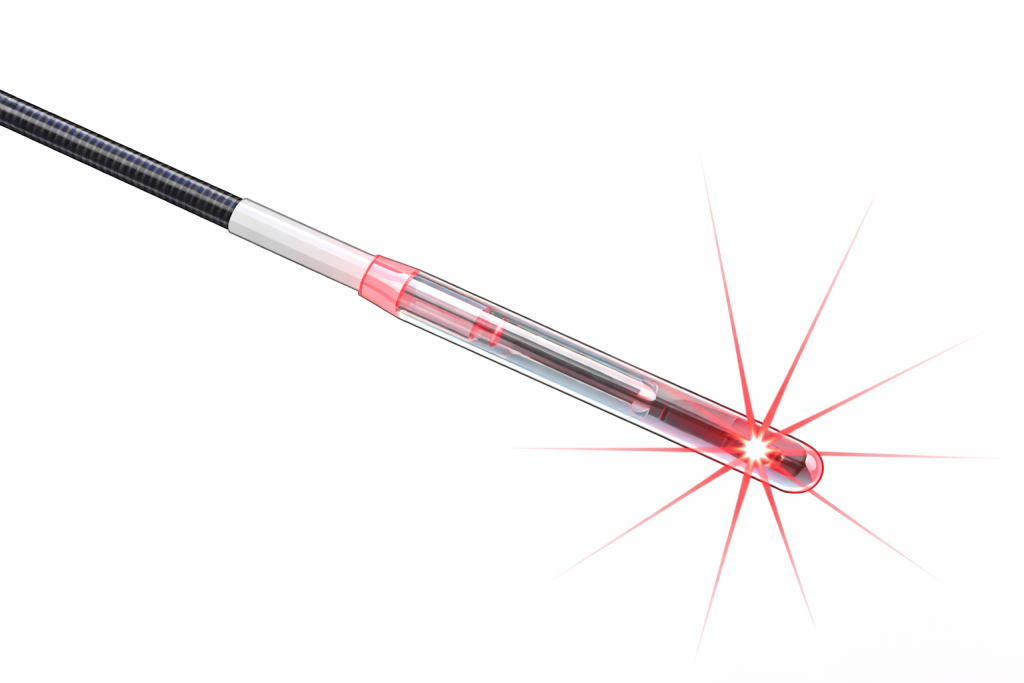

LÁSER 600 MICRAS

La extirpación es quirúrgica guiada por láser 600 micras, de forma ambulatoria, con muy buena recuperación postoperatoria y buen control del dolor en lesiones de pequeño tamaño y número.

20min

Local y sedación

Ambulatoria

Resultados del Láser 600 micras

- Eliminación completa de las lesiones (cercana al 100%) en el momento del procedimiento.

- Altísimo grado de satisfacción, por rapidez y mínima agresión.

- Dolor muy leve o prácticamente inexistente en la mayoría de pacientes.

¿Cómo es el postoperatorio?

- Procedimiento ambulatorio, con alta el mismo día.

- Reincorporación rápida a la vida normal.

- Mínima inflamación y cicatrización rápida, con molestias leves y controlables.

¿Cirugía extensa o mínimamente invasiva?

La cirugía mínimamente invasiva con láser ofrece menos dolor, menos complicaciones y una eliminación más precisa de las lesiones.